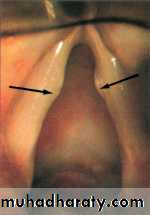

They are bilateral, small, grayish, white,localized thickening of the vocal cords

situated at the junction of the anterior

third and posterior 2/3 of the vocal cord.

In this area maximum vibration occurs followed by fibrosis and traumatic scarring.

The site of nodule is at the junction of the anterior third and posterior 2/3 of the vocal cord.